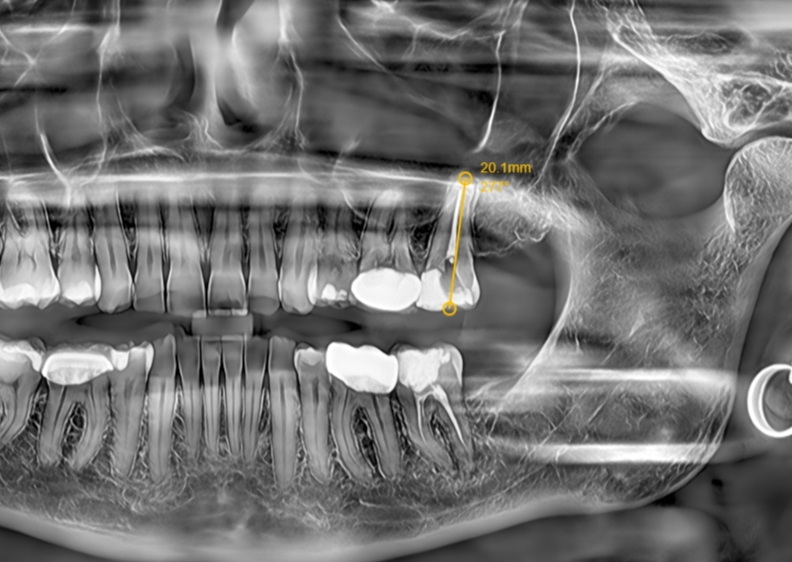

In contrast, dental implant restoration after tooth extraction can restore the masticatory hardness of the tooth, and the implant can form a stable osseointegration with the jawbone. However, dental implants have an inherent physiological limitation—they lack the pressure-sensing mechanism of the periodontal ligament. Patients cannot precisely control the magnitude of occlusal force during mastication; excessive occlusal force is prone to induce peri-implant bone resorption and loosening, ultimately leading to implant failure. In addition, the long-term survival of dental implants is highly dependent on rigorous postoperative maintenance, including professional cleaning care and regular follow-up examinations, making their maintenance significantly more challenging than that of natural teeth after root canal therapy.

Therefore, in clinical practice for pulpitis-affected teeth, root canal therapy should be prioritized to preserve natural teeth. Dental implant restoration should only be considered when the affected tooth is severely damaged and cannot be retained via root canal therapy. Furthermore, it is essential to fully inform patients of the advantages, disadvantages, and postoperative maintenance requirements of both treatment modalities.